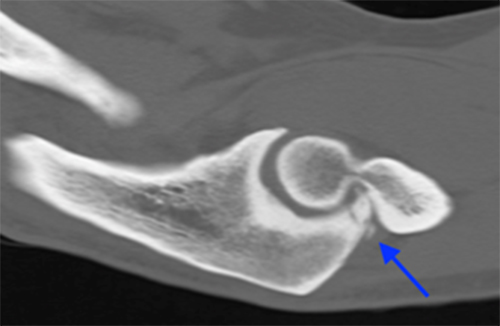

- CT scan is best for identifying loose bodies and osteophytes for surgical planning

CT scan demonstrates posteromedial osteophytes within the olecranon fossa